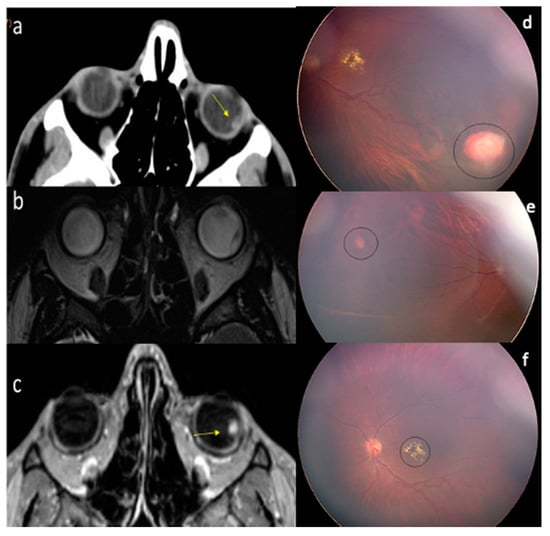

2. Case Report